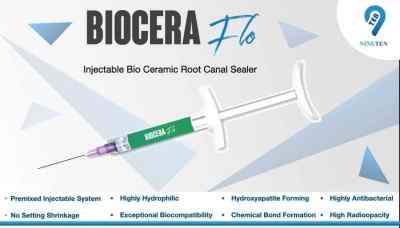

NT Biocera Flo Bioceramic Root Canal Sealer

- Model : NT Biocera Flo Bioceramic Root Canal Sealer

NT Biocera Flo Bioceramic Root Canal Sealer - 1 Unit

NT Biocera Flo Bioceramic Root Canal Sealer is an advanced bio-compatible injectable bio-ceramic sealer developed for dental applications. Biocera Flo serves several crucial purposes within the dental practice, primarily for permanent teeth root canal procedures, either with or without Gutta Percha Points. It also excels as a sealer in retreatment cases and proves effective in managing internal resorption cases. Dental professionals can choose between two convenient application methods. They can opt for direct injection using preloaded syringes equipped with disposable intracanal plastic flexible tips for precision. Alternatively, they can follow the conventional technique, which involves dispensing the sealer on a mixing pad and introducing it into the canal using GP points or lentulo spirals. To ensure safe usage, it's imperative to exercise caution. Dental practitioners should wear safety goggles, masks, and gloves when working with Biocera Flo. Furthermore, it's essential to safeguard the product against moisture exposure and prevent cross-contamination by using absolute oral isolation and refraining from reusing applicator tips. Proper storage conditions are essential to maintain the product's efficacy. Biocera Flo should be stored in a dry, well-ventilated environment with temperatures ranging between 5°C and 25°C and relative humidity levels below 60%. Refrigeration is not suitable for storage.

Composition:-

- Calcium Silicates

- Calcium Aluminate

- Calcium Hydroxide

- Zirconium Oxide

- Accelerators

- 1 x 2gms Premixed injectable syringe.